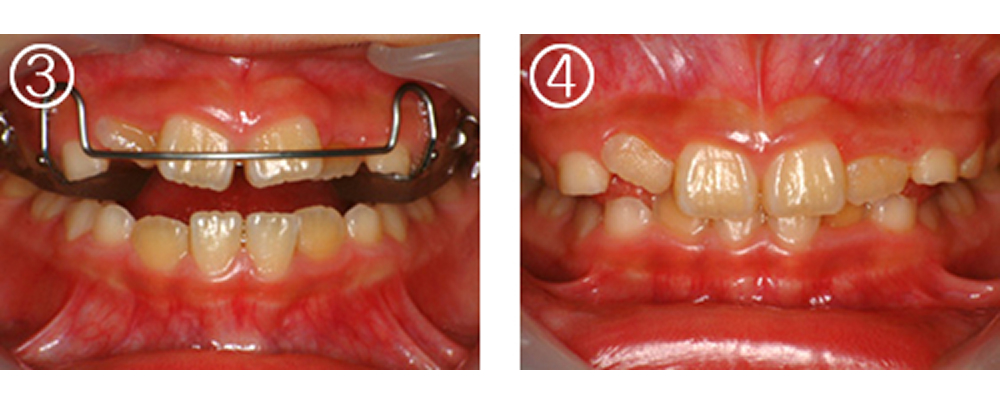

①術前:8歳 4前歯が反対咬合で歯が並ぶスペースも不足

②拡大床(エキスパンジョンスクリュー 床矯正装置)を作製

③装着した所

④4ヵ月後 反対咬合が改善し、歯が並ぶスペースも確保できた。ここまできていれば永久歯列になったときの矯正は簡単です